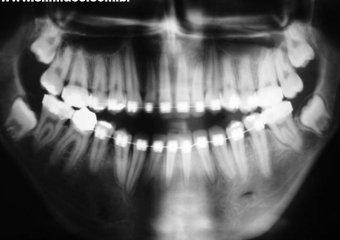

Raio x panorâmico inicial